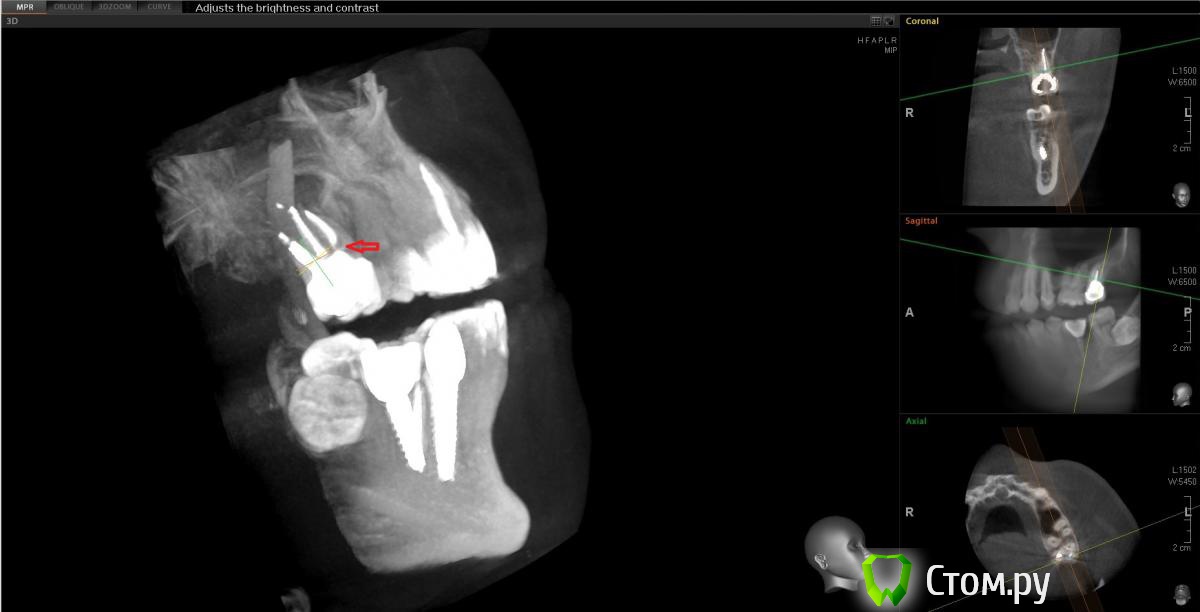

Еще один прицельный снимок этого зуба. Есть вариант того, что там пропущен канал?[/url]

Сначала предположила что есть пропущенный канал исходя из этого:

Но оказалось, что это как бы "пора"